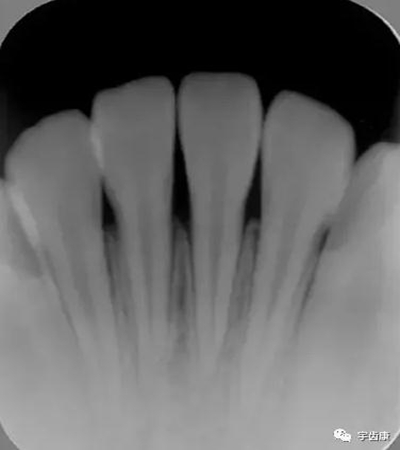

X線閱片知識

牙體解剖知識

牙體各個面的解剖厚度